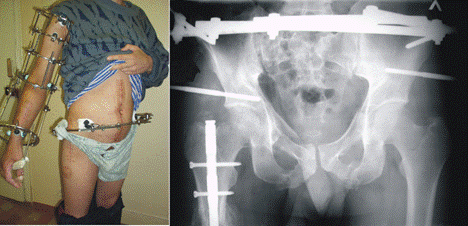

При оперативном лечении на проведенных в кости таза стержнях монтируют аппарат, с помощью которого выполняют репозицию (рис.12). По достижении репозиции аппарат переводят в режим стабилизации сроком на 5 – 6 нед. Трудоспособность восстанавливается через 10–12 нед.

![]() |

Рис.12. Чрескостный стержневой остеосинтез в лечении переломов типа В2.